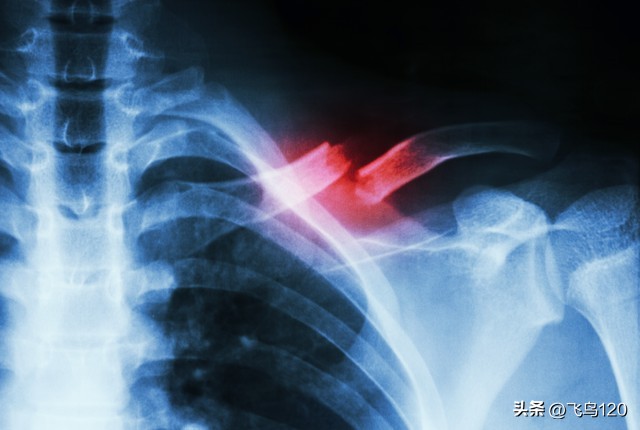

而且她这骨头的毛病还挺大,大夫看了片子,说她骨质疏松的特别厉害,相当于60岁老人的骨头,想不通啊,一个三十多岁的女人,骨质怎么会这样。

这张照片,我自己看了,都感觉吓人啊,骨头上全是眼,到底是什么原因?不健康的饮食,还是?